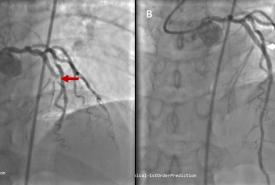

Early Recognition and Intervention of De Winter Syndrome: A Case Report

Case Report 27 Jan, 2025

Wan Asyraf Wan Zaidi

• Read more about Wan Asyraf Wan Zaidi